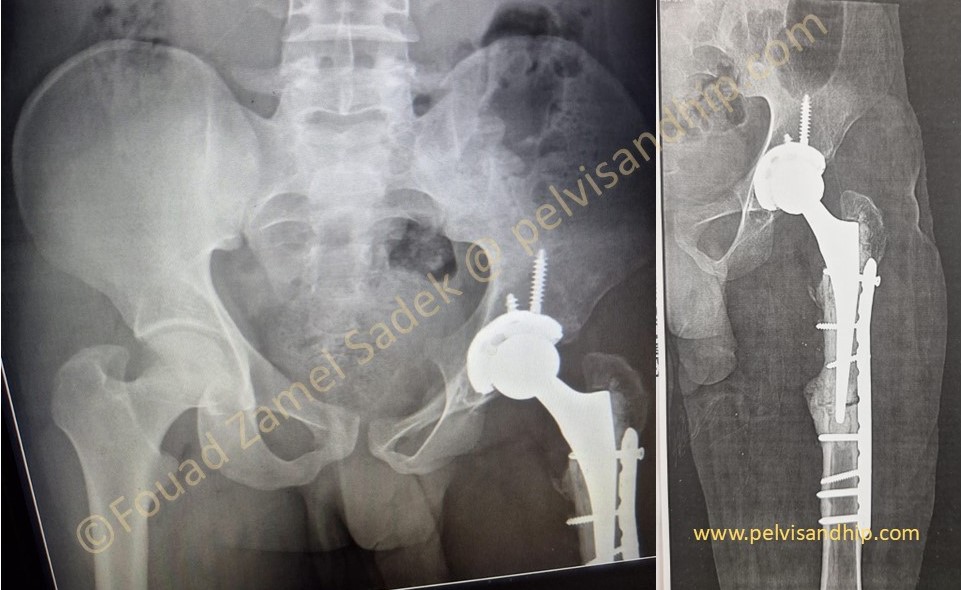

At 3 months follow up. Patient is walking full weight bearing with no support. The amount of union at the osteotomy site is quite reassuring.

7 months after surgery patient is allowed to carry out all activities with no restrictions. The abundant callus formation is obvious with nearly complete healing of the femoral osteotomy.